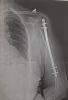

• Копия рентгенографии плечевого сустава (2 шт.)

Целью проведения данной судебно-медицинской экспертизы являлось всестороннее изучение представленных материалов гражданского дела и медицинских документов для установления ключевых аспектов, связанных с характером и степенью тяжести телесных повреждений. Перед экспертами стояла задача не только определить вид полученных повреждений, но и проанализировать механизм их образования, а также установить их причинно-следственную связь с обстоятельствами дорожно-транспортного происшествия, изложенными в исковом заявлении и административном материале. Работа требовала тщательного сопоставления различных источников информации, включая показания участников происшествия и детали медицинской документации. Основная сложность заключалась в реконструкции последовательности событий и идентификации факторов, приведших к травме, исключительно на основании представленных записей и описаний, без непосредственного осмотра объекта исследования. Экспертами были применены методы структурного и системного анализа, а также визуально-аналитический подход к изучению текстовых и графических материалов. Особое внимание уделялось интерпретации рентгенологических снимков, которые являлись критически важным элементом для объективной оценки характера перелома. Это позволило сформировать комплексное представление о механизме травмы и потенциальных условиях её возникновения. Одним из важных аспектов стала необходимость определения давности образования выявленных повреждений на основе медицинских данных, что требовало глубоких знаний в области судебной медицины и травматологии.